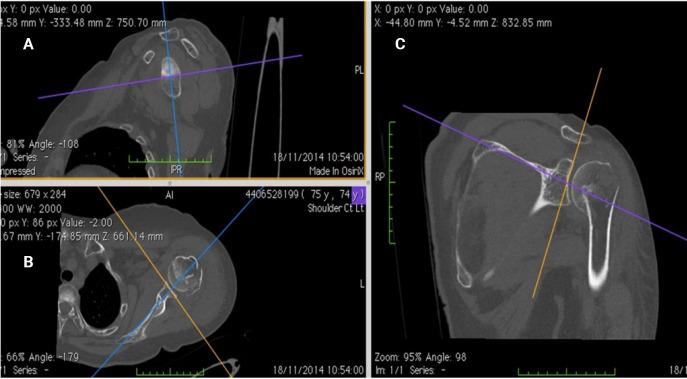

Accurate measurement of glenoid version is essential for optimal implant positioning in shoulder arthroplasty. This study compared the accuracy and reliability of unformatted two-dimensional computed tomography (2D-CT), formatted 2D-CT, and three-dimensional CT (3D-CT) reconstructions in measuring glenoid version.

METHODS

Shoulder CT scans for arthroplasty were analyzed retrospectively. Glenoid version was measured at the estimated glenoid midpoint using unformatted and formatted 2D-CT in the scapular plane. Measurements from 3D-CT reconstructions using the Corrected Friedman Method were used as the control. Inter- and intra-observer reliability was calculated as well as minimally detectable difference.

准确测量肩胛盂版本对于肩关节置换术中最佳植入物定位至关重要。本研究比较了未格式化二维计算机断层扫描(2D-CT)、格式化2D-CT和三维CT(3D-CT)重建在测量肩胛盂版本方面的准确性和可靠性。

方法

对用于关节置换术的肩部CT扫描进行回顾性分析。在肩胛平面中使用未格式化和格式化的2D-CT在估计的肩胛盂中点测量肩胛盂版本。使用校正弗里德曼方法从3D-CT重建中获得的测量结果用作对照。计算观察者间和观察者内的可靠性以及最小可检测差异。